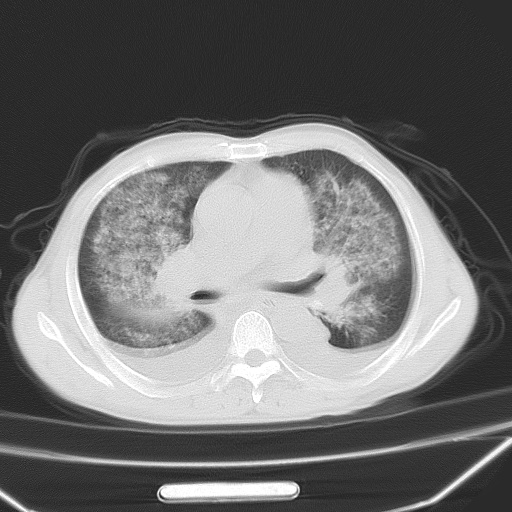

男、42岁、咯血3天。既往有甲亢、贫血、血尿蛋白尿史多年。血象:wbc:6.   中性粒:70.6%。

双肺野对称性磨玻璃影,分布于内中带,双侧胸水,患者有咯血。

双肺野广泛对称性磨玻璃影、实变影,以肺门为中心,主要分布于内中带,符合典型肺泡性肺水肿;伴双侧胸腔少量游离积液。结合患者既往病史且咯血就诊,支持多因素(尿毒症等)所致之肺水肿、肺出血、胸水;影像表现暂不考虑心源性水肿,且症状也不太符。需密切随诊结合临床治疗等进一步明确。